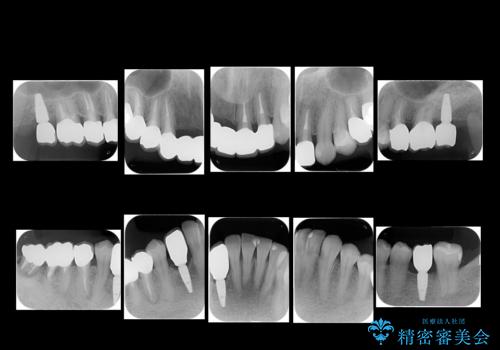

- 全体的な虫歯治療、根管治療、および歯周病治療を行いました。

歯周病治療につきましては歯周ポケット除去のために歯周外科処置(APF)を行っています。

左下6の欠損については左下7はワイヤー部分矯正でアップライトを行い、補綴スペースを確保しています。

右下犬歯は歯周病の進行が重度のため、やむなく抜歯をし、骨増生後にインプラント埋入を行っています。